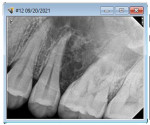

A 32-year-old healthy man, referred by his general dentist, presented with mild numbing sensation symptoms on the left aspect of his maxilla. Four months before the referral, when the patient had no symptoms, a panoramic radiograph revealed the splaying of teeth. Possibly because of the superimposition of radiopaque structures, this went unnoticed. Upon the author's clinical examination, a CBCT revealed a well-defined, multilocular radiolucent lesion present between teeth Nos. 13 and 14. The general behavior of the lesion was rather aggressive. Biopsy results confirmed ameloblastoma, a common benign tumor of the jaws that requires marginal resection due to its high recurrence rate. A treatment plan with the surgical and restorative team was presented to the patient. The treatment would begin with a hemimaxillectomy with secured margins and mucocutaneous fibula graft with implant placement at the time of resection. After 6 months of healing, the second-stage surgery would follow with the insertion of a 3D-printed long-term temporary restoration. Several months later, after occlusion changes and complete healing, the final prosthesis would be inserted. The case was completed in 12 months using a digital workflow plan (DEXIS, dexis.com) that involved the use of intraoral scanning, virtual surgical planning (VSP) software, advanced imaging, exocad software, 3D printing, and more.